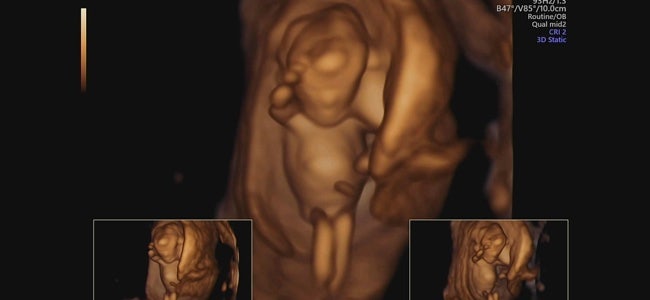

임신29주 - 정밀입체초음파, 시그바리스압박스타킹 구입

안녕하세요. 29주가 되어 정밀초음파 볼겸 병원에 다녀왔어요. 맘카페보니 26주쯤으로해서 다들 찍으시던데...